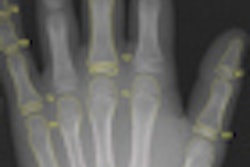

Fifty-six patients (58.3%) had abnormal bone mineral density as measured by dual-energy x-ray absorptiometry (DEXA) scan of the lumbar spine (L1-L4), with osteopenia in 42 and osteoporosis in 14. There were significant differences between the patients and controls in bone mineral density, z score, and body mass index.